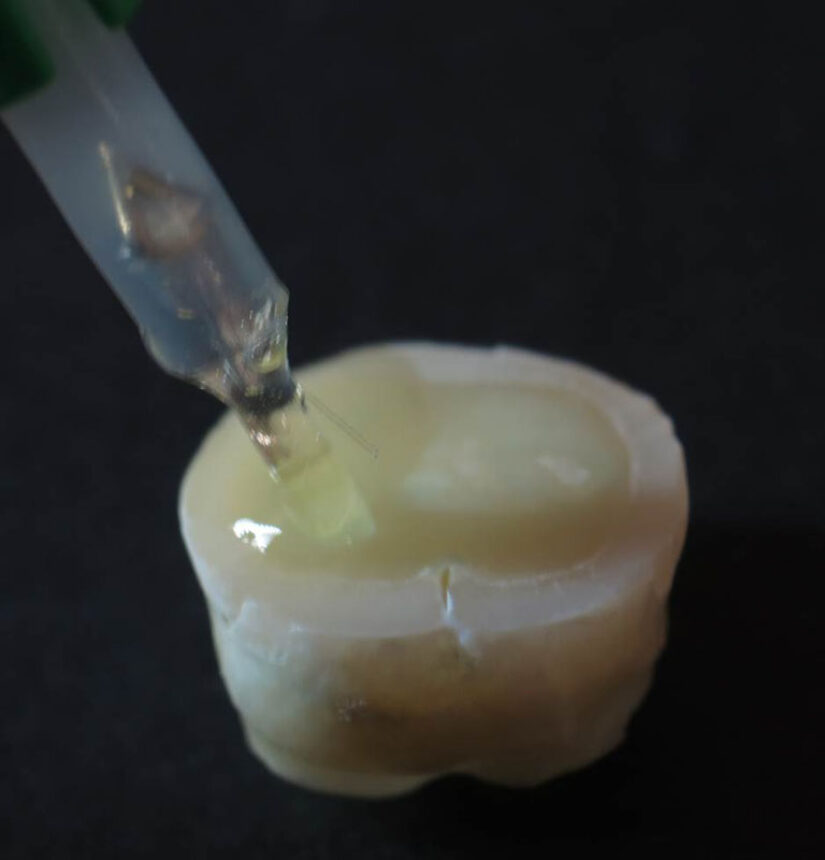

Κάθε αποκατάσταση οπισθίων δοντιών με σύνθετη ρητίνη στοχεύει στη φυσική χρωματική απόδοση και σωστή ανατομική μορφολογία αλλά και στην προστασία του βιολογικού και λειτουργικού υποβάθρου του δοντιού. Γιατί ωστόσο επικρατεί σύγχυση με τα ποικίλα κλινικά πρωτόκολλα και υλικά για τις εμφράξεις με σύνθετες ρητίνες; Γιατί εμφανίζεται μετεπεμβατική ευαισθησία; Ποια σύνθετη ρητίνη είναι η κατάλληλη και ποιος συνδετικός παράγοντας θα προσφέρει τη μεγαλύτερη αντοχή; Πόσο υγρή πρέπει να είναι η οδοντίνη για τη σωστή συγκόλληση; Τι ρόλο παίζει η συσκευή πολυμερισμού που θα χρησιμοποιηθεί; Ποιο είναι το σωστό τοίχωμα για κάθε περίπτωση αποκατάστασης; Και αφού όλα έχουν γίνει σωστά, γιατί ο ασθενής πονάει; Είναι όντως οι σύνθετες ρητίνες τόσο απλές και καθημερινές όπως ένας καφές; To webinar συνοψίζει τις απαντήσεις στα σύγχρονα κλινικά ερωτήματα, συνθέτοντας τη συνταγή για επιτυχημένες εμφράξεις σύνθετης ρητίνης με υλικά που απλοποιούν τη διαδικασία και τεχνικές, tips & tricks που μιμούνται τη φύση.